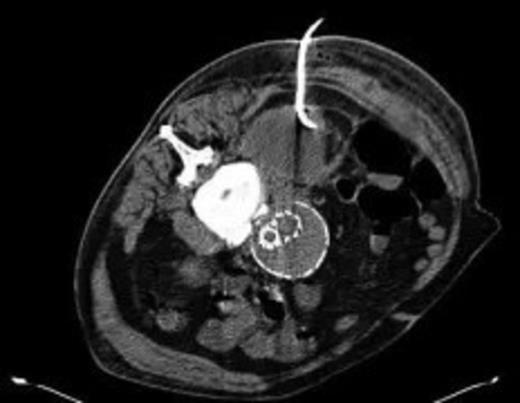

Four weeks following discharge the patient was re-admitted with feeling increasingly unwell, recurrent pyrexia, loss of appetite and mild shortness of breath on exertion. Physical examination was unremarkable except for a temperature of 38.3 centigrade. Blood tests on admission showed Hb 11.4 g/dl (11.5-16.0 g/dl), white cell count 13.1×109/L (4-9.2 x 109/L) and CRP 68mg/L (<3 mg/L). Contrast enhanced CT scan (Fig. 2,3) showed a 50 mm maximum retroperitoneal collection situated between the right kidney and the right iliac vessels. It contained a few loculi of gas. A diagnosis of postoperative right psoas abscess was made. The patient was started on intravenous broad spectrum antibiotics – Tazocin (Piperacillin+ Tazobactam) and Metronidazole. CT guided drainage was carried out using a 10 French gauge pigtail catheter locked pigtail (Meditech Flexima regular all-purpose drainage catheter sets with locking pigtail (Boston Scientific)) (Fig. 4). The isolation of E. coli from the collection with negative Hemocultures suggested a bowel source for the infection but no actual breach was demonstrable. The bowel surgeons ruled out colonic pathology.

CT guided drainage was carried out using a 10 French gauge pigtail catheter locked pigtail (Meditech Flexima regular all-purpose drainage catheter sets with locking pigtail (Boston Scientific))

The patient's condition improved quite rapidly and the intravenous antibiotics were stopped and replaced with oral ciprofloxacin upon microbiological advice (for a total of six weeks). The drain was removed after 2 weeks when the series of repeat CT scans showed the abscess had nearly completely resolved (Fig. 5). Further CTs on follow up at 6 weeks and 3 months post discharge show no collection at all. At the last clinic visit 6 months following his last admission the patient was enjoying good health.

Near complete resolution of psoas collection after 2 weeks of intravenous antibiotics